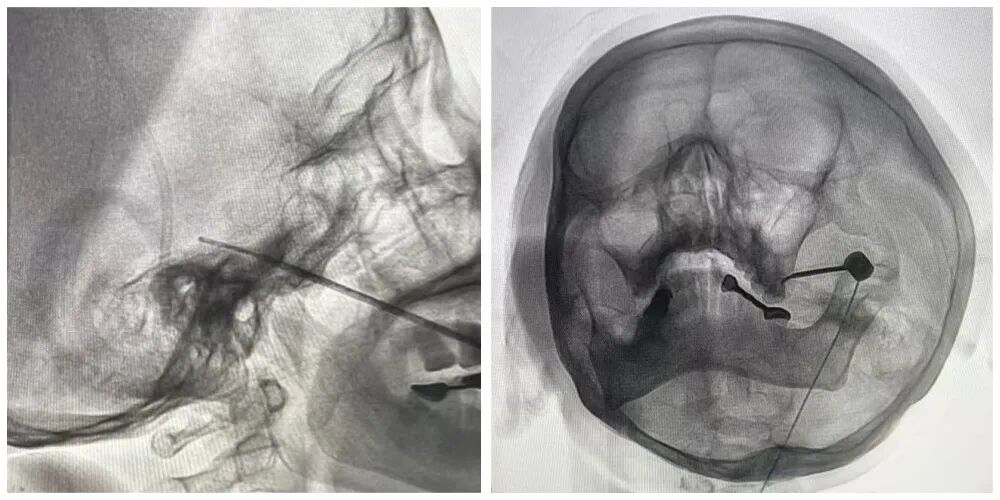

手术过程中,王主任在精准定位下,将一根穿刺针插入三叉神经出入颅腔部位卵圆孔,进而释放一个小小的球囊压迫数分钟,来捣毁传导神经痛的“中转站”,手术仅用时一小时便顺利完成。